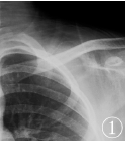

X线片:左肩胛骨见椭圆形膨胀性囊样骨破坏(图1);

图1 左肩关节X线平片示:左肩胛骨区呈膨胀样低密度影,边缘包绕薄骨壳